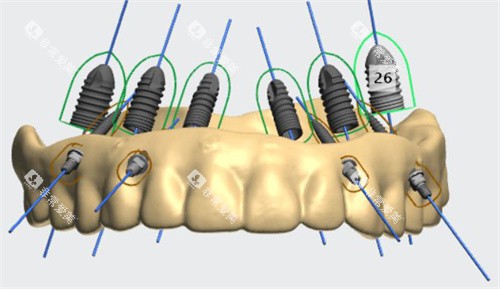

(三)半口和全口种植牙

半口种植牙

价格区间:3 万 - 10 万元

全口种植牙

价格区间:6 万 - 20 万元

项目介绍:价格根据种植体的数量和品牌而定,能为患者提供稳固、美观的牙齿修复改善。